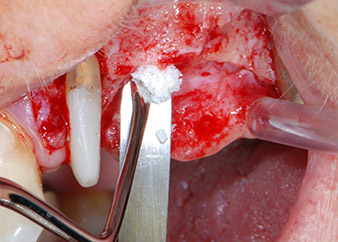

Antes de la colocación del implante y tras la verificación de que la membrana de Schneider estaba intacta (figura 9), la base interna del seno se aumentó en las dos posiciones del implante con un material sustituto de hueso xenógeno (Bio-Oss, Geistlich Biomaterials) (figura 10).

A continuación, los implantes (Restore, Keystone Dental, 3,75 mm de diámetro, 8,0 mm de longitud) se colocaron con el motor de implantes (figuras 11 y 12).